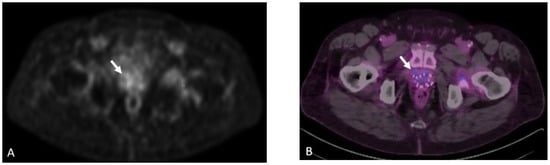

Detection of Loco-Regional Disease and Distant Metastases